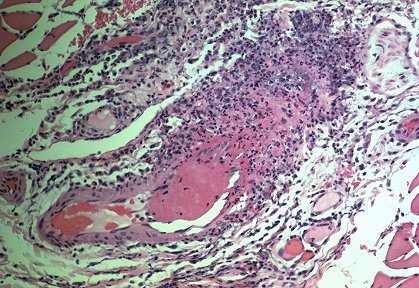

| Necrotizing arteritis in a skeletal muscle biopsy. Note the segmental transmural necrosis and inflammation with an adjacent thrombus. |

![]() |

I think everyone here has a clear understanding of what vasculitis is. Of course, it is inflammation of vessel walls. It is not inflammation around vessels; it is inflammation of vessel walls. The vasculitis that affect the kidney most often are necrotizing vasculitides that affect parenchymal arteries and also in fact very often vessels other than arteries. You could say vessels smaller than arteries, but it's really more definitive to say vessels other than arteries. Today we are really going to be concerned with necrotizing vasculitis affecting arteries and other smaller vessels.